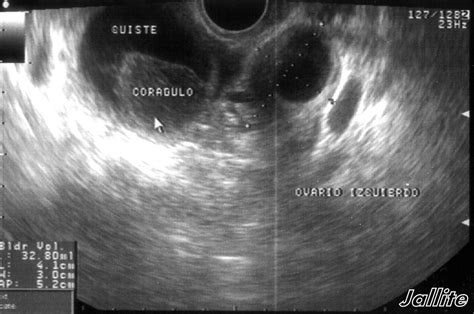

• Ultrasound: This imaging test uses sound waves to create images of the ovaries and can help determine the size, location, and type of cyst.